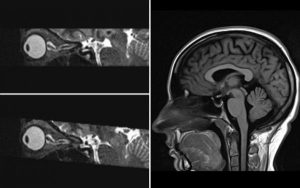

Chronic spinal pain and radiculopathy: Diagnostic approach and common imaging pitfalls